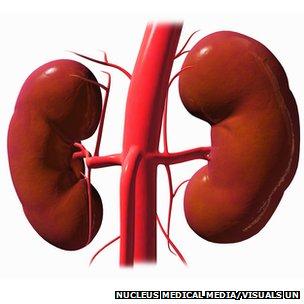

Kidney

Renal artery/vein